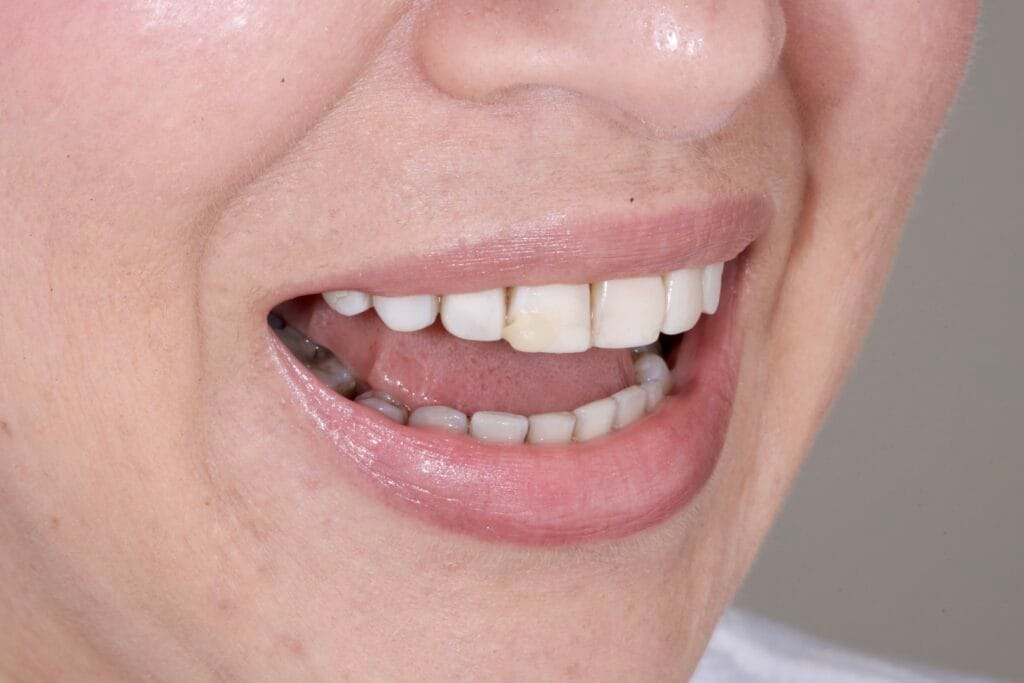

Our patient arrived with an existing resin smile design that no longer met her expectations. Over time, the restorations became completely disadapted and compromised both aesthetics and function. As a result, margins deteriorated, proportions lost balance, and the smile stopped integrating harmoniously with her facial features.

Additionally, we faced a significant challenge: a deviated dental midline. Therefore, this case required a precise and thoughtful approach guided by facial analysis in smile design.